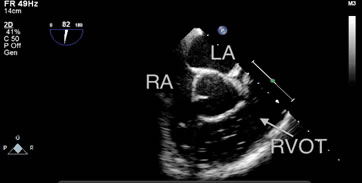

One patient in the S group experienced a severe GE (grade 5) with low blood pressure and ETco2 values, and bubbles filling the RA and RVOT, as detected by TEE (Figure 2 and Video 1). However, the patient was discharged from the hospital without any complications.

Figure 2: Bubbles filling the RA and RVOT were detected by TEE in one patient in the S group during hepatic parenchymal resection. The patient exhibited notable hypotension and a decrease in end-tidal carbon dioxide (from 37 mmHg to 12 mmHg). RA: right atrium, LA: left atrium, RVOT: right ventricular outflow tract.

One patient in the S Group exhibited cardiorespiratory instability during the hepatic parenchymal resection. The reason for this may have been be that the entry of CO2 through the open middle hepatic vein in a short time led to a state of circulation failure, with a notable reduction in ETco2 (from 37 mmHg to 12 mmHg) and subsequent lung hypoperfusion. The TEE monitor displayed the amount of gas accumulating in the RVOT (Figure 2 and Video 1). The transient accumulation of gas in the pulmonary artery caused an “air lock” of the right heart cavities and reduced inflow into the left side of the heart, which could have induced acute hypotension or even cardiac arrest. Overall, the clinical influence of GE depends on the balance between the volume of gas entering the circulation and the amount of gas that is removed [21].